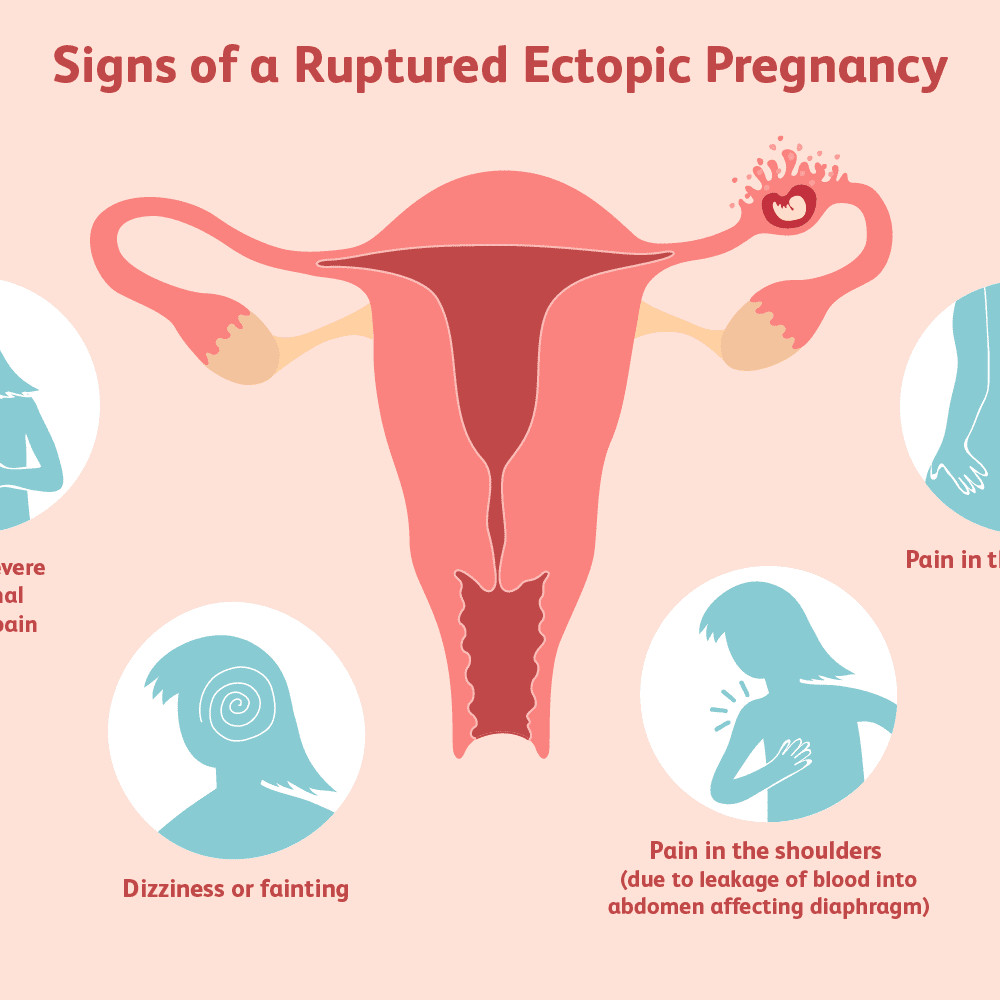

Kehamilan Ektopik Terganggu

Kehamilan ektopik terganggu (KET) adalah ketika sel telur yang terbuahi tertanam di luar rahim lalu pecah dan mengalami perdarahan.